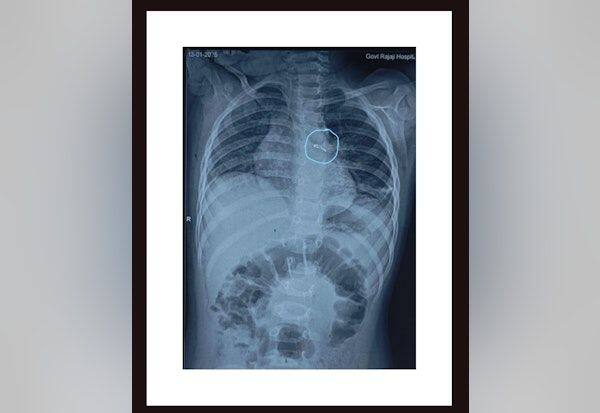

மதுரை அனுப்பானடி தம்பதியின் ஒரு வயது பெண் குழந்தை தொடர் காய்ச்சல், இருமலால் அரசு மருத்துவமனையில் சேர்க்கப்பட்டார். ஸ்கேன் பரிசோதனையில் மூச்சுக்குழாயின் இடதுபுறத்தில் ஊக்கு போன்ற பொருள் இருந்தது தெரிந்தது.

மயக்கவியல் துறை இயக்குநர் கல்யாணசுந்தரம், நெஞ்சகநோய் மருத்துவப்பிரிவு துறைத்தலைவர் பிரபாகரன், குழந்தைகள் அறுவை சிகிச்சை துறைத்தலைவர் மீனாட்சிசுந்தரி தலைமையில் 'பிராங்கோஸ்கோப்' கருவி மூலம் 2 மணி நேர முயற்சிக்கு பின் மூச்சுக்குழாயில் இருந்த ரிமோட் காரின் எல்.இ.டி. பல்பு வெளியே எடுக்கப்பட்டது. தற்போது குழந்தை நலமுடன் உள்ளது.

ஒரு மாதத்திற்கு முன்பாக மற்றொரு தம்பதியின் ஒருவயது ஆண் குழந்தையின் மூச்சுக்குழாயில் சிக்கியிருந்த நிலக்கடலை இதே முறையில் அகற்றப்பட்டது. நவம்பரில் திண்டுக்கல் குட்டத்துப்பட்டி 8 மாத பெண் குழந்தையின் நுரையீரல் இடதுபக்க மூச்சுகுழாயில் சிக்கிய 'ரிமோட்' காரின் 'எல்.இ.டி., லைட்' 'பிராங்கோஸ்கோப்பி' கருவி மூலம் அகற்றப்பட்டது. இக்குழந்தை இருமல், மூச்சுத் திணறல், காய்ச்சலுடன் திண்டுக்கல் அரசு மருத்துவமனையில் இருந்து மேல் சிகிச்சைக்காக மதுரை அரசு மருத்துவமனைக்கு அனுப்பி சிகிச்சை அளிக்கப்பட்டது.